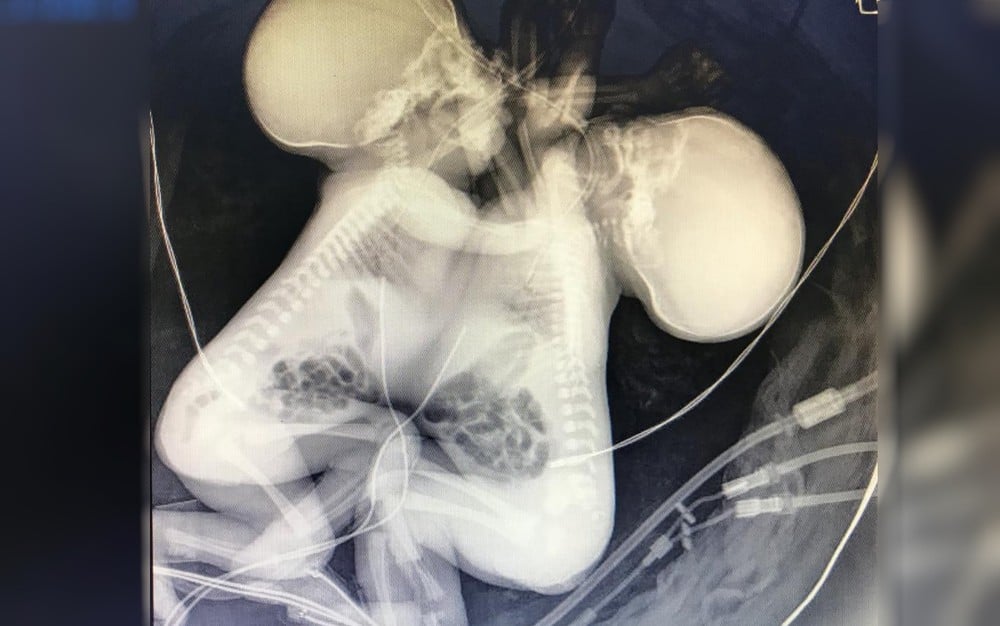

Luto Gêmeas siamesas que compartilhavam o coração morrem no Materno Infantil, em Goiânia As gêmeas siamesas que compartilhavam o mesmo coração morreram no Hospital Materno Infantil (HMI), em… há 6 anos